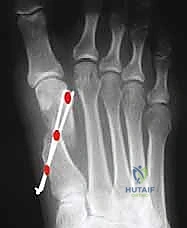

الخطوة الرابعة: الإزاحة والتصحيح (Translation and Correction)

بمجرد اكتمال القطع، يتم إزاحة رأس العظم المشطي بحذر نحو الجانب الخارجي للقدم (لإغلاق الفجوة بين المشط الأول والثاني). في هذه المرحلة، يتم أيضاً تدوير رأس العظمة لتصحيح زاوية (DMAA) إذا لزم الأمر. يتم التأكد من استقرار العظام السمسمانية في مكانها الصحيح أسفل المفصل.

تُظهر الصورة كيف يتم دفع رأس العظم المشطي إلى مكانه التشريحي الصحيح، مما يقضي على الزاوية المرضية ويعيد للقدم استقامتها.